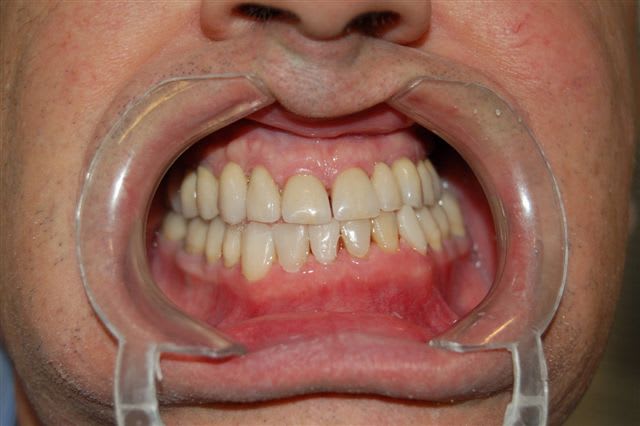

de retour au cabinet je peux vous poster les différentes étapes de ce que j'ai réalisées pour ce patient dans le cadre de l'OSB afin de me faire mousser et non de partager avec vous une expérience qui m'a parue intéressante comme alternative à la cavalerie lourde proposée par certains d'entre vous à savoir la chirurgie...

Validation de cette nouvelle occlusion par le patient pendant 6 mois puis si tout baigne prothèse fixe céramique, globale dans ce cas.

Cas terminé en décembre 2006, revu la semaine dernière, ce qui m'a donné envie de vous le montrer.

voilà les photos excusez moi d'en avoir doublé une, , quant à la dernière, c'est celle de la semaine dernière.